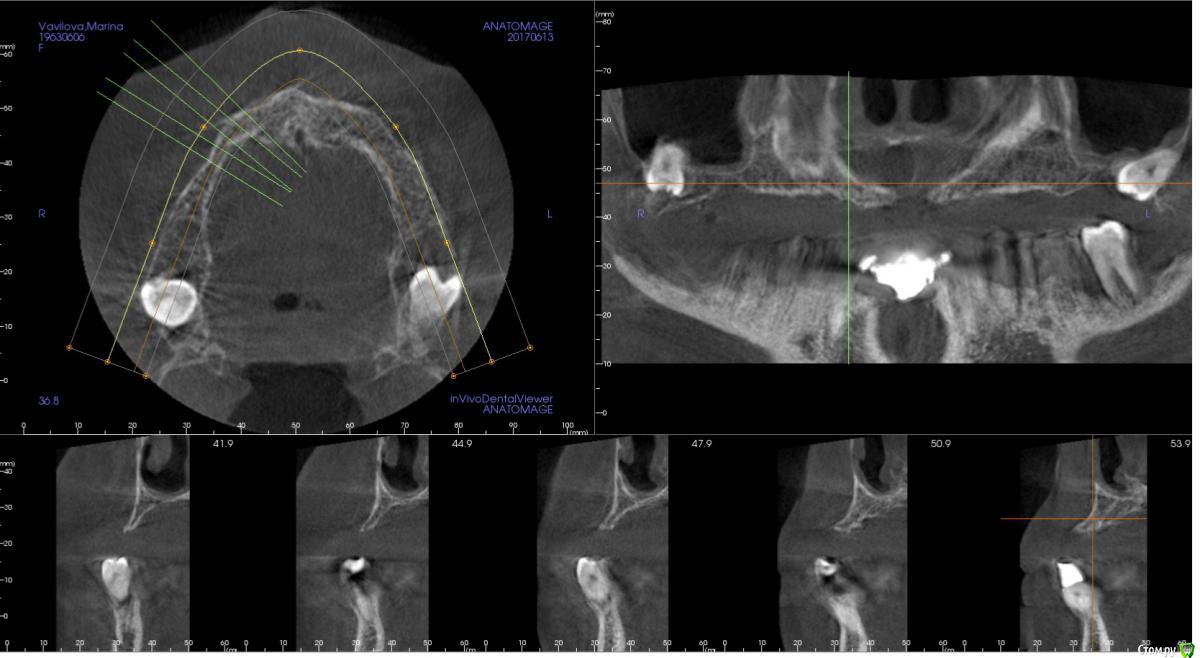

kamranchick Опубликовано 2 ноября, 2017 Поделиться Опубликовано 2 ноября, 2017 (изменено) Планируется установка 3 имплантатов в 1 сегменте, и будет балочная конструкция.хочется пойти двухэтапным протоколом. так как гигиена и вредные привычки меня отпугивают.Какой вариант тут будет предпочтительным Изменено 2 ноября, 2017 пользователем kamranchick Ссылка на комментарий

kamranchick Опубликовано 2 ноября, 2017 Автор Поделиться Опубликовано 2 ноября, 2017 А сколько всего планируется имплантов? А если только во фронте 4 поставить?6 имплантатов, 3 с одной поставил, теперь 3 с другой, во фронте кости кот наплакал( Ссылка на комментарий

Тимур86 Опубликовано 2 ноября, 2017 Поделиться Опубликовано 2 ноября, 2017 яб синус лучше сделал Ссылка на комментарий

kamranchick Опубликовано 2 ноября, 2017 Автор Поделиться Опубликовано 2 ноября, 2017 Гигиена просто катастрофа.Балка чтобы конструкция была условно сьеигаячСинусы планирую тоже сделать.А насчёт зигом ну это слишком)))) Ссылка на комментарий

zzkz Опубликовано 3 ноября, 2017 Поделиться Опубликовано 3 ноября, 2017 согласен за синус и отсроченную нагрузку через 6 мес Ссылка на комментарий